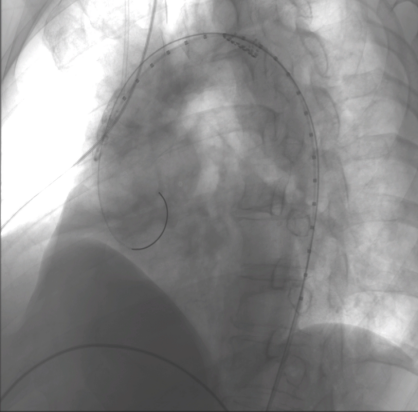

第一例患者术中造影

第二例患者术中造影